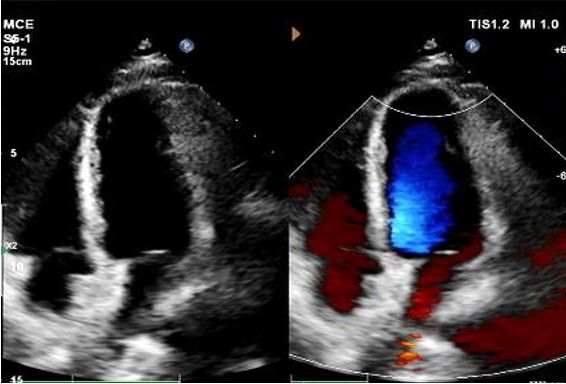

1 yıllık eko:

No visible disc structures – replaced by 8mm tissue thickening at the septal implant site.

Zero residual shunt (rest or post-Valsalva).

Komple cihaz emilimi onaylandı.